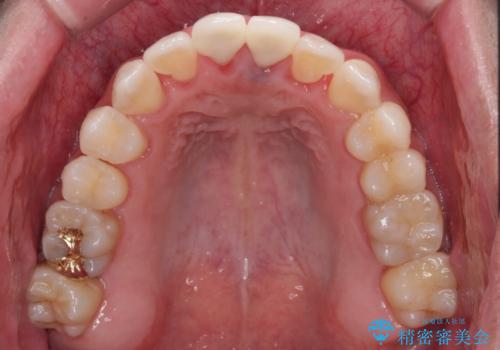

歯肉の腫脹は大分改善されましたが、なかなかご自身でのブラッシングが上達せず、やや腫脹残った状態での治療終了となりました。